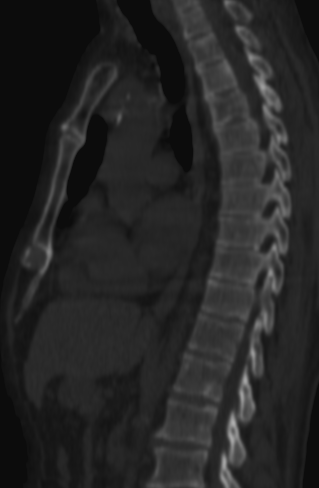

Image

a

b

c

d

5. Multiplex bone metastases. Bone scintigraphy, anterior (a) and posterior (b) whole body scans. SPECT-CT sagittal plane, fusion image (c) and CT image (d). Obvious bone structural changes cannot be identified on the CT scan yet.

The examination is appropriate for staging a malignant process and following-up bone metastases. It is clinically most suitable for lesions that frequently present bone metastasis, primarily in case of prostate-, breast-, lung cancer and neuroblastoma. It is, however only indicated in cases where the soft tissue involvement of the tumor is big enough to suggest a higher incidence of bone metastasis; before radical surgeries and for the selection of patients who would benefit form a palliative radionuclide therapy. Otherwise, scintigraphy is advisable in case of any primary tumor, if the suspicion for metastasis is raised, e.g.: bone pain, pathologic radiological or lab results (elevated serum ALP and tumor marker levels). Bone metastases in most cases are located in bones that contain red bone marrow (skull, vertebrae, ribs, sternum, pelvic bones and the proximal bone segments of the limb) and usually show a multiplex appearance. Activity increase can be seen typically, metastases that cause activity decrease are rare; they could occur in cases of thyroid gland tumor, renal carcinoma, lymphoma and multiple myeloma. Solitary lesions or a few lesions only, due to the aspecific nature of the examination, cause a differential diagnostic problem in many cases, for example vertebral degenerative processes can mimic metastatic activity. Equivocal lesions usually require further, targeted radiological investigations. A negative X-ray examination does not rule out the possibility of a metastatic lesion, since the isotope scan is more sensitive. Therefore, it is possible that it could already be detecting an existing metastasis, while X-ray is still insensitive and unable to show the lesion. (Figure 5.)